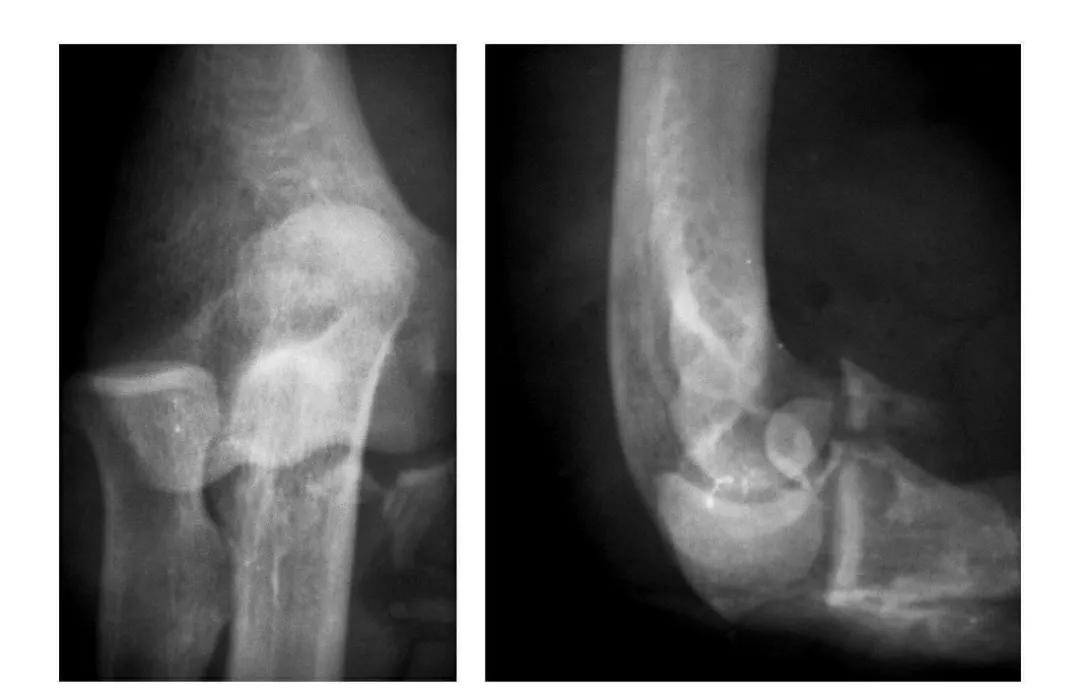

例1:肱骨滑车及尺骨冠状突发育不全,致肘关节不稳而呈习惯性脱位。

例2:尺桡骨近端发育不全,致肘关节不稳而呈习惯性脱位。